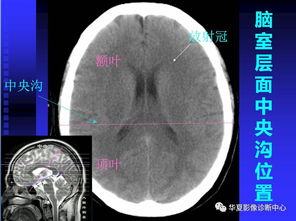

磁共振成像術(shù)的空間分辨室,也有待進一步提高。(一)顱腦與脊髓 MRI對腦腫瘤、腦炎性病變、腦白質(zhì)病變、腦梗塞、腦先天性異常等的診斷比CT更為敏感,可發(fā)現(xiàn)早期病變,定位也更加準(zhǔn)確。